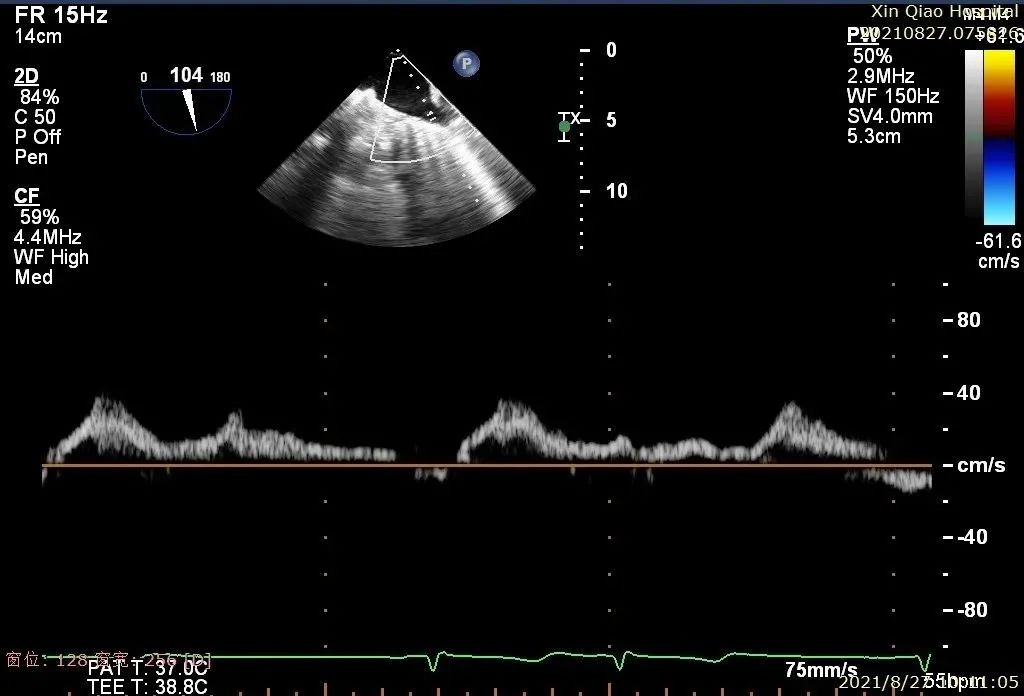

患者术后B超图

术后即刻,患者反流显著减小,二尖瓣反流从4+减少到1+以下,左房压下降,血流动力学改善明显,手术取得了圆满成功。